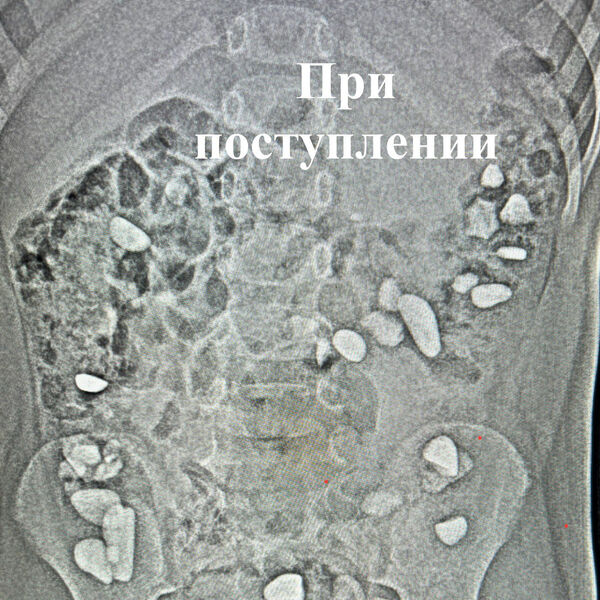

Недавно в Ессентукскую городскую клиническую больницу поступил ребенок, который проглотил более 25 камней. Это выяснилось во время рентгенологического исследования, и его родители не знали, при каких обстоятельствах все произошло.